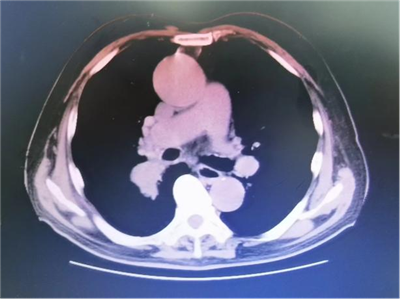

患者陈伯伯因为反复胸闷、气喘10年,加重伴咳嗽、咯血1月入院,胸部CT提示:右肺下叶近肺门处占位伴阻塞性炎症,肺气肿,心影增大。入住我院胸心血管外科后,床位医生张屹为其进一步完善相关检查,制定优质的诊疗方案,建议陈伯伯手术治疗。但在选择手术方案时遇到了难题,胸部CT所示,患者气管肿瘤的位置正好位于右肺中间段支气管,紧临上叶支气管开口,如果采取传统的术式,为保证切缘距离,需要牺牲患者右上叶,做右侧全肺切除,手术风险较高,术后肺功能恢复慢,病人生活质量差。

术前胸部CT:肿瘤累及中间段气管紧邻上叶气管